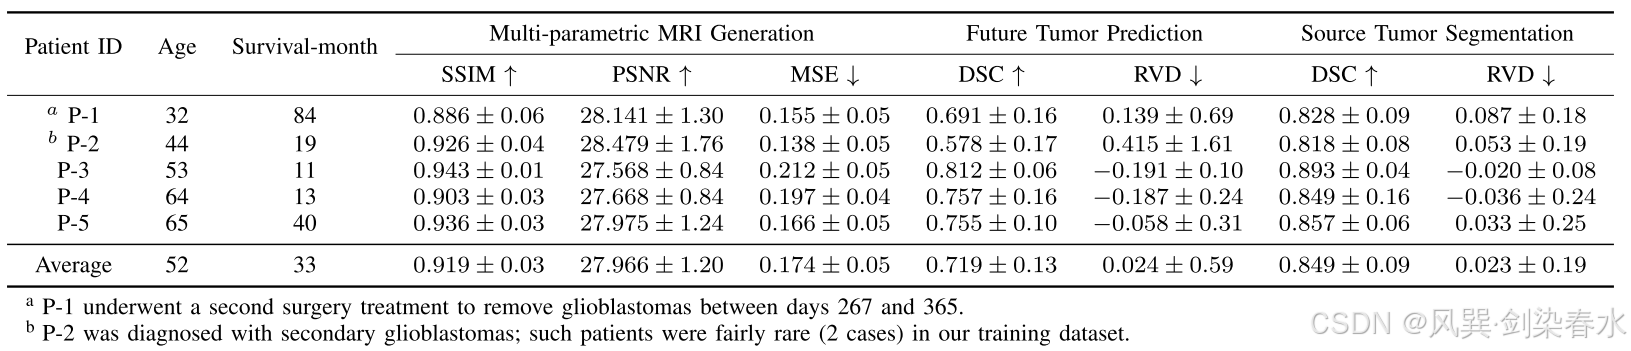

Table 1 | 测试集结果:

Table 2 | 治疗天数定量结果: